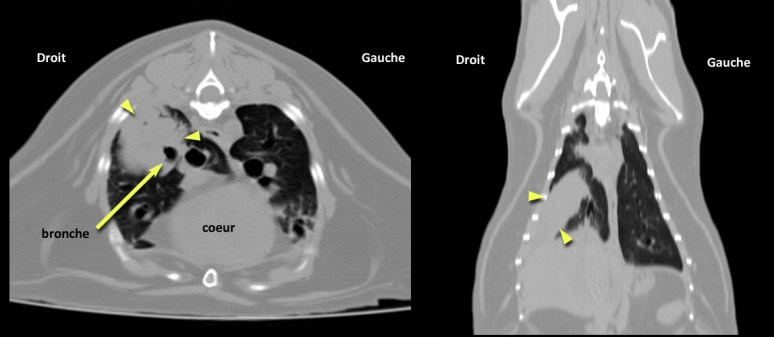

Comme la silhouette cardiaque était arrondie, on pouvait effectivement penser que l’augmentation d’opacité en région caudodorsale était associée à de l’oedème. Toutefois, les vaisseaux pulmonaires paraissaient normaux et la rondeur du coeur pouvait s’expliquer par la présence de gras péricardique chez ce patient obèse. Traiter avec un diurétique et recommander une échocardiographie restait toutefois une proposition valable. Compte tenu de l’âge de ce chat et de l’asymétrie de l’augmentation d’opacité pulmonaire, un processus tumoral devait aussi être envisagé. Une échographie aurait pu permettre de confirmer cette suspicion par le biais d’une cytoponction, si la masse se trouvait accolée à la paroi. Chez ce chat, une tomodensitométrie (CT, scanner) a été effectuée (images du bas) afin d’obtenir un portrait global des poumons et d’exclure la possibilité de métastases pulmonaires et abdominales. Une masse au contour irrégulier a été identifiée au lobe caudal droit, entourant une bronche principale aérée. Un carcinome bronchoalvéolaire a été fortement suspecté sur la base d’une cytoponction échoguidée. Le reste des poumons ne montrait pas de métastases franches, mais quelques foyers d’atélectasie… À suivre…